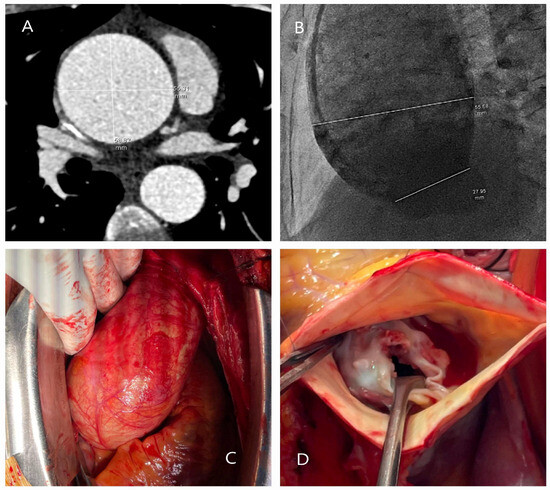

5.2.3. Computed Tomography